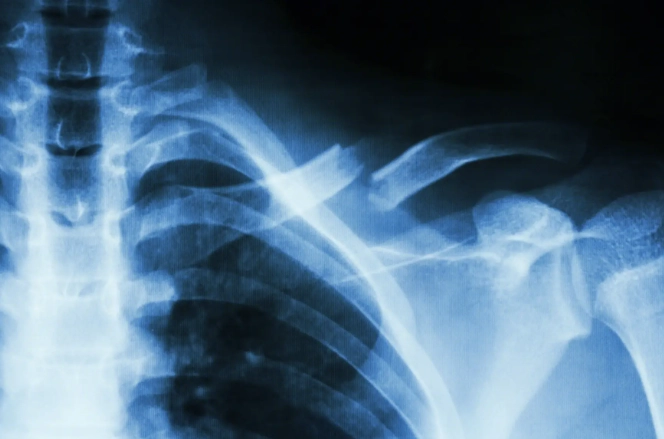

肋骨骨折後,身體會啟動自然的愈合過程,包括炎症期、修復期和重塑期。這段期間,營養攝取直接影響骨骼的再生能力。如果吃了不該吃的東西,可能會干擾這些階段,導致恢復延遲或併發症。例如,高鹽分食物會引起水腫,增加胸腔壓力,讓呼吸都變得更痛苦。而辛辣食物則可能刺激神經,加劇疼痛感。

有些研究指出,飲食控制能減少併發症風險,比如肺炎或感染。肋骨骨折常伴隨呼吸困難,如果飲食不當導致腹脹或炎症,可能會讓呼吸更吃力。這點我深有體會,當初因為貪吃鹹酥雞,結果水腫搞得我連深呼吸都痛,真是自作自受。